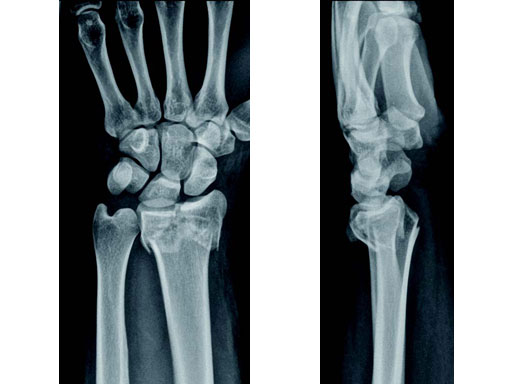

22-year-old male fell off a horse while playing polo.

Case provided by Ladislav Nagy, Zrich, CH

Fig 1a-b Preoperative x-rays.